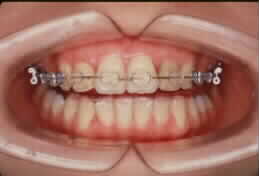

矯正装置というと金属のぎらぎらしたものを

思い浮かべる方も多いと思います。

でも今は目立たない透明な装置もあるので心配いりません。